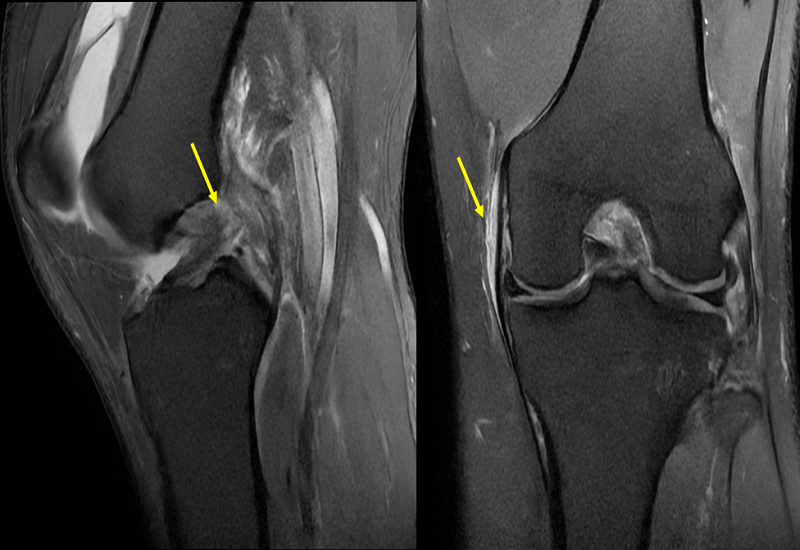

Chụp MRI khớp gối là gì? Quy trình thực hiện thế nào?